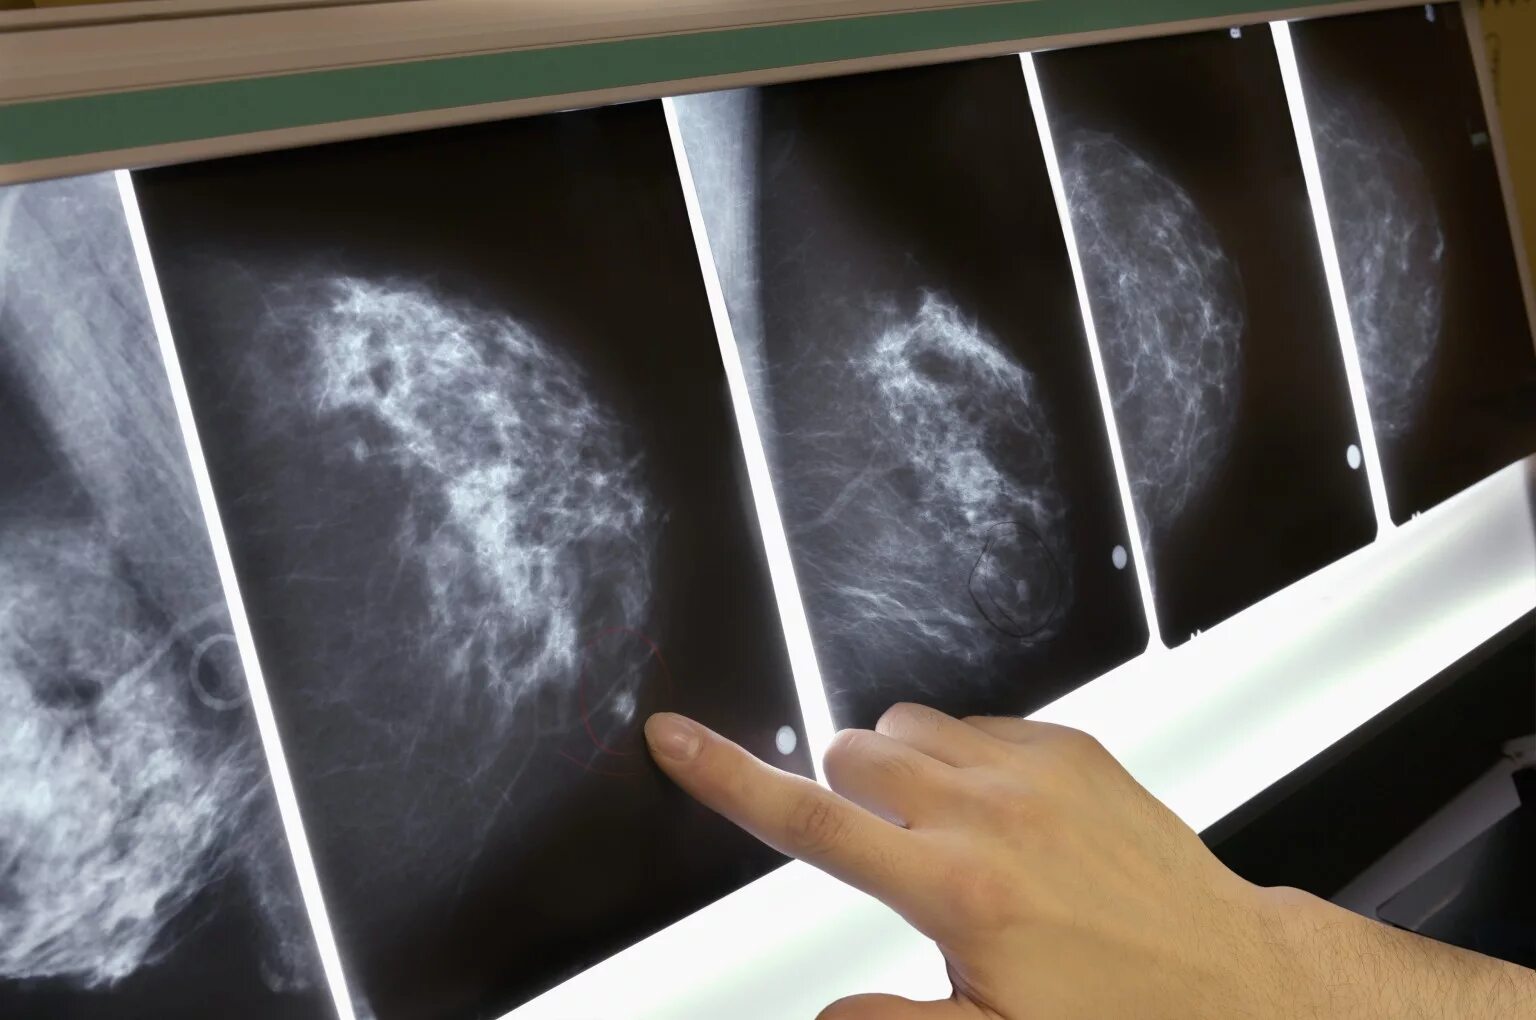

Опухолевидное образование молочной железы